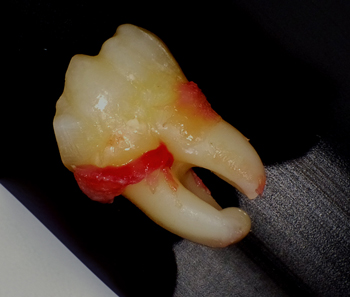

抜歯開始から30分程で無事に抜歯が終了。

上記の3D画像からも分かるように内側(舌側)への傾斜もきつかったため、歯を分割する際、「舌を傷つけない」事に最も気を配りました。